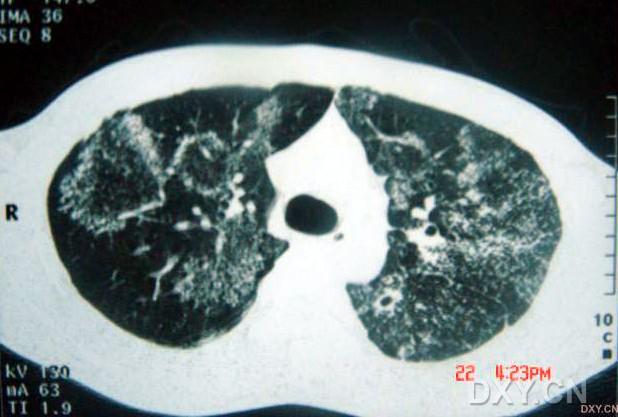

影像表現(xiàn):

兩肺彌漫性顆粒狀陰影,部分陰影融合呈團塊狀,可見支氣管氣相;

呈非對稱,非均勻分布性,部分肺野呈磨玻璃密度;

多處胸膜局限性增厚,胸水征(--)縱隔窗為正常。